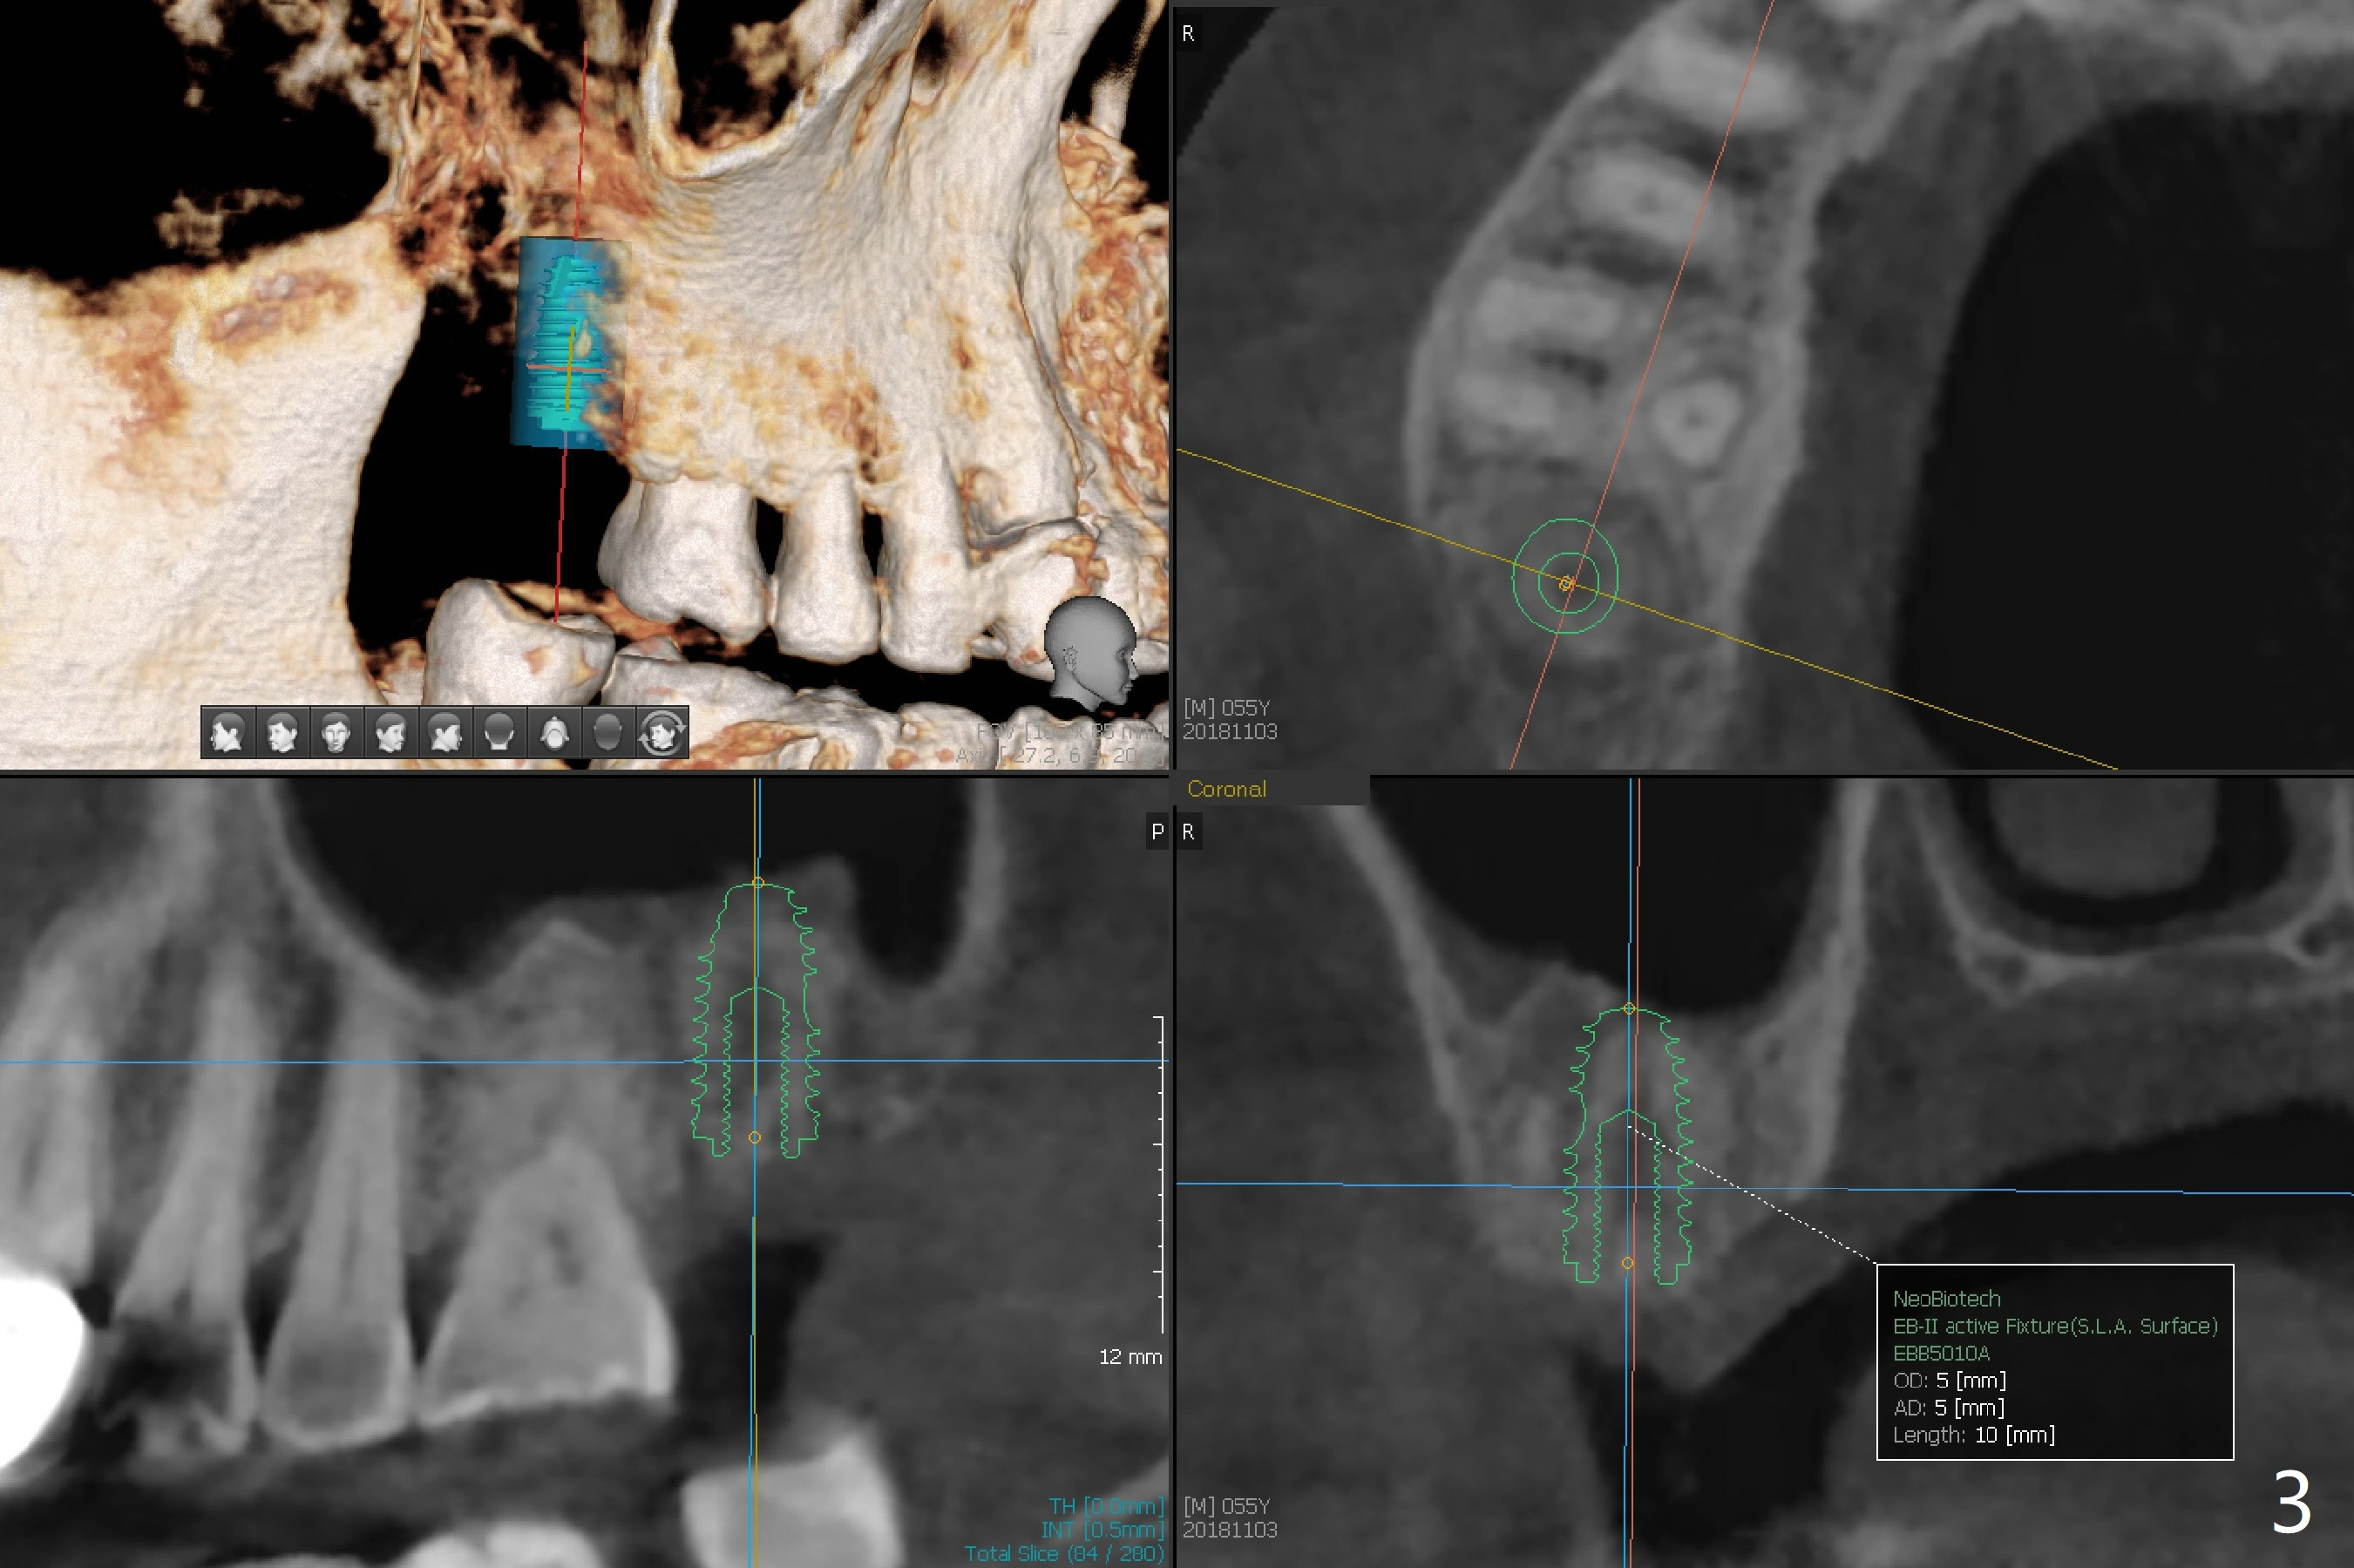

A 55-year-old man with chronic sinusitis, gagging and bruxism returns for #2 implant redo nearly 4 months post implant removal and bone graft (Fig.1). It appears that the site heals with ~ 860 HU (Fig.2). Considering history of chronic sinusitis, a 5x10 mm implant seems too long (Fig.3). For active gag reflex, a 5x11.5 mm implant may be also too long at #19 (Fig.4).